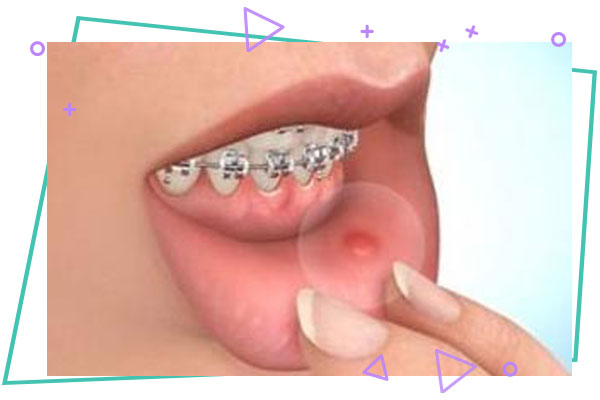

اولین شرط دارا بودن بهداشت مطلوب دهانی می باشد. زیرا به علت چسبانده شدن براکت ها روی دندان ها، مواد غذایی بیشتری روی آن ها تجمع می کنند و باید مرتب تمیز گردند . در صورت عدم رعایت بهداشت دندان ها، احتمال پوسیدگی دندان ها بیشتر می شود . از دیگر شرایط ارتودنسی ثابت ، ترمیم کلیه دندان های خراب و وحود بافت سالم می باشد. همچنین مراجعات منظم و رعایت توصیه پزشک از دیگر موارد موفقیت درمان محسوب می شود.

با توجه به چسبانده شدن براکت ها و دندان ها باید هنگام غذا خوردن از صدمه شدید به آن ها جلوگیری شود . چون این امر باعث کنده شدن و اتلاف وقت جهت چسباندن مجدد آن ها می شود . همچنین باید با رعایت بهداشت ، استفاده از مسواک ها و نخ دندان های مخصوص از ایجاد پوسیدگی روی دندان ها جلوگیری شود . در مورد دستگاه های متحرک ، نگهداری آن ها به شکل صحیح و استفاده مداوم از آن ها و مراجعات منظم از موارد مهم و موفقیت درمان می باشد .